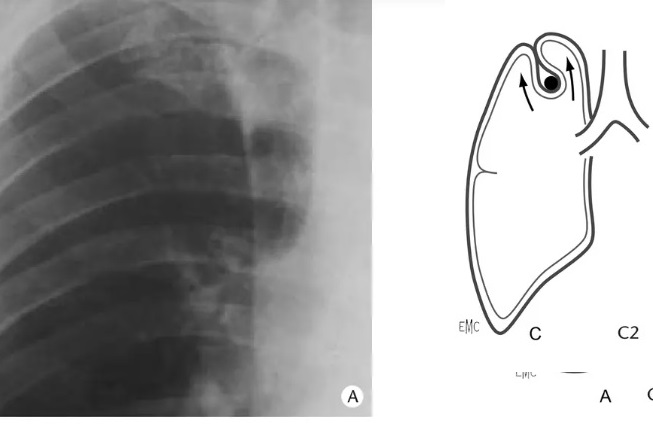

Aspect radiologique de

veine Azygos sur cliche pulmonaire de face

. Le trajet du veine est engager si profonde

dans apexdu poumon et contourne completement

par la plevre parietale et viscerale |

Meme

cas en coupe TDM axiale à travers D3 , apex du

poumon . La scissure Azygos etre en vue comme

une bande hyperdensite du pomon droit . Image

radiologique TDM en coupe axiale , fenetre

mediastinale |

De même cas de

image radiologique normale de scissure ascessoire Azygos

en coupe TDM axiale fenetre parenchymateuse à travers

coupole du poumon ( TH3 , TH4 )

|

Même cas en coupe TDM

coronal ( frontale ) fenetre parenchymateuse

. La plie de scissure ascessoire Azygos est en

vue tres nette à droit de superieure du hile

droit . |